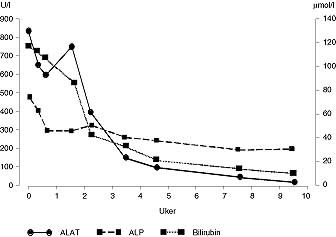

Pasient 3 . 30 år gammel kvinne. Hun fikk meningitt fire år gammel og fra tiårsalderen epilepsi. Det ble startet behandling med fenytoin, som pasienten brukte frem til hun var 22 år gammel. Man skiftet da til karbamazepin. Seks måneder senere ble hun innlagt i medisinsk avdeling. Hun hadde da vært ikterisk i seks dager, men var for øvrig uten allmennsymptomer. Resultatet av blodprøvene er vist i tabell 1. Det ble mistenkt medikamentell hepatitt, og karbamazepin ble seponert. ANA ble påvist svakt positiv, og ved serumelektroforese var det polyklonal økning i gammaregionen. Paul-Bunnells prøve og antistoffundersøkelse med hensyn på hepatitt A-virus og hepatitt B-virus var negative. Behandling med fenytoin ble gjenopptatt etter utskrivningen, men seks år senere ble fenytoin igjen seponert til fordel for karbamazepin på grunn av manglende anfallskontroll. 21 måneder etter dette ble hun så på nytt innlagt i medisinsk avdeling. I motsetning til første gang hadde hun nå følt seg slapp, kvalm og uvel i ti dager. Hun hadde anoreksi med gjentatte brekninger. Ved innkomst var hun afebril, BT 105/80 mm Hg og puls 64 regelmessig. Hun var i god allmenntilstand, men tydelig ikterisk, for øvrig var det intet påfallende ved klinisk undersøkelse. Blodprøver viste også denne gangen patologiske leververdier (tab 1). Karbamazepin ble igjen seponert, pasienten kom seg gradvis. Forløpet av blodprøvene er vist i figur 2. ANA var sterkt positiv, med en titer på 1 024 som var uforandret to måneder etter utskrivningen. IgG var forhøyet, med en verdi på 24,9 g/l (referanseområde: 6,9 – 15,7 g/l), og var fortsatt forhøyet ved kontroll to måneder senere, med en verdi på 23,6 g/ l. Verdiene for IgA og IgM var hele tiden normale. Leverbiopsi ble utført og viste akutt og kronisk betennelse med fibrose, tegn til nekrose av parenkymceller og kolestase. Ultralyd lever og galleveier viste mulig ødem i galleblæreveggen med omliggende fibrotiske forandringer, men ingen konkrementer. Antistoff mot hepatitt A-virus eller hepatitt B-virus ble ikke påvist, og det var normale verdier for ceruloplasmin og alfa-1-antitrypsin. 12 år senere viste nye blodprøver fortsatt forhøyet ANA, med en titer 256, og IgG-fraksjon i serum på 17,5 g/l.